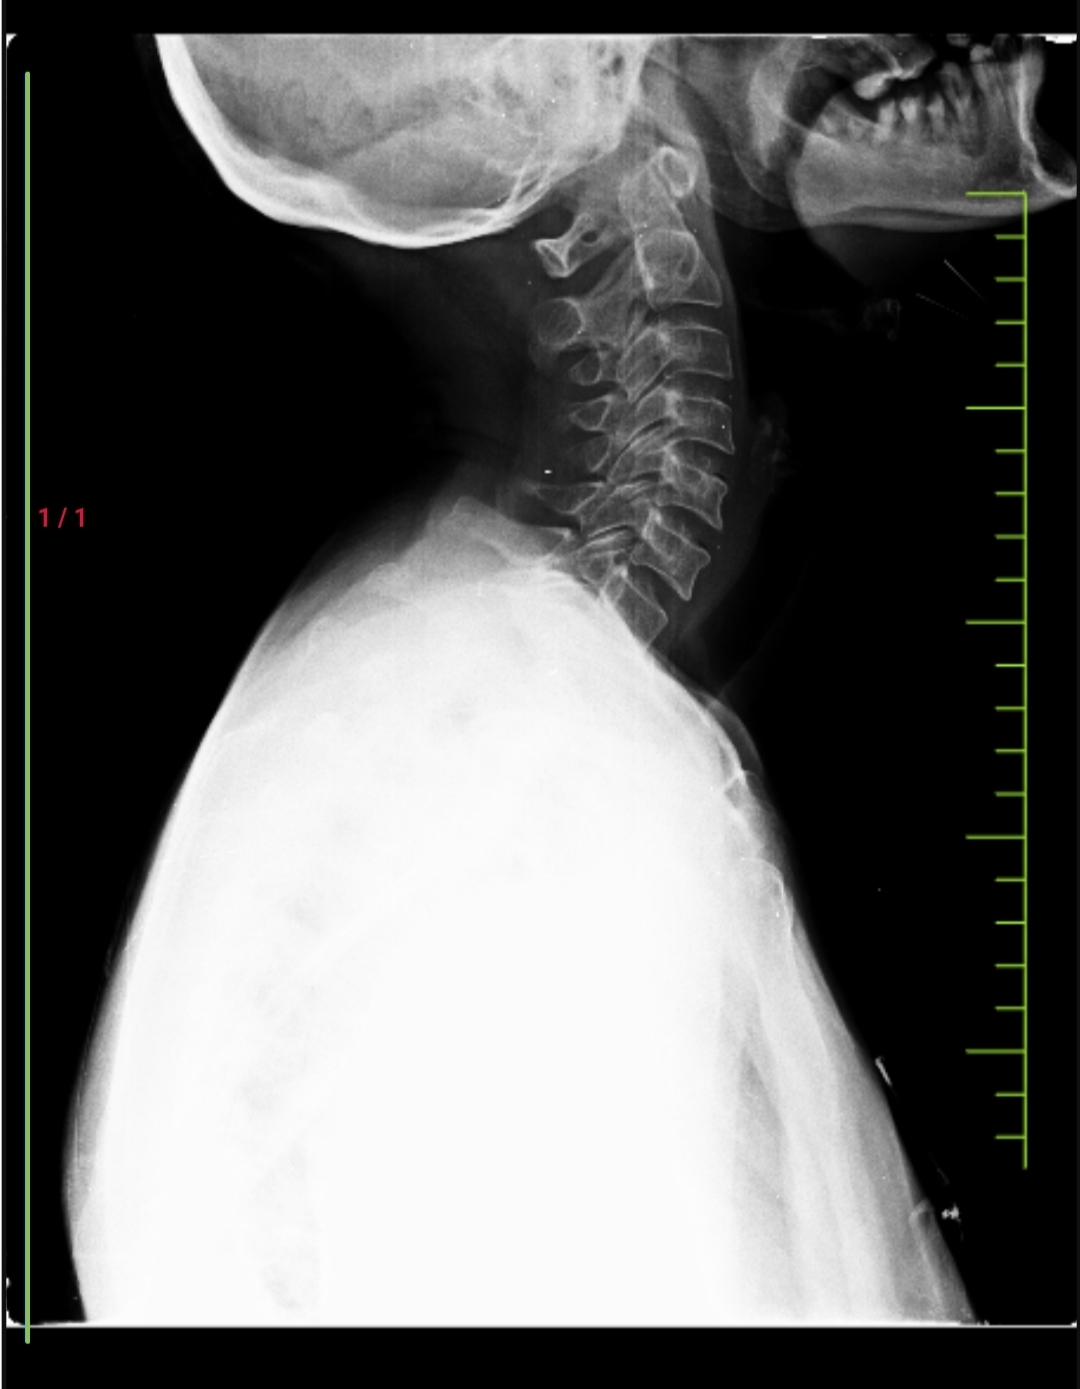

X-ray spine:

Impression:

Mild degenerative changes notes in the cervical spine.